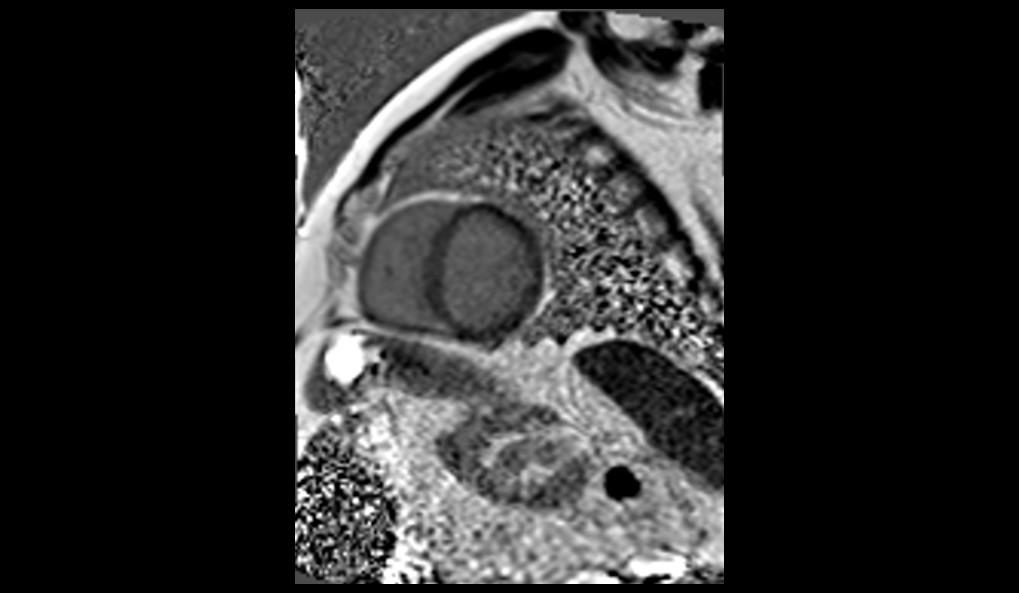

El examen de RMC se realizó en el equipo MAGNETOM Altea 1.5T. Se realizaron secuencias de CINE PSIF, FSE black-blood T1 y T2, phase-contrast, mapeo miocárdico (MyoMaps) T1/T2/T2* y LGE TRUFI high-resolution después de la inyección de contraste (DOTA-Gd 0,5M 0,2mmol/kg).

La RMC evidenció dilatación biatrial importante (AD=170ml/m2 y AE=120ml/m2), dilatación biventricular discreta (VDFVD=115ml/m2 y VDFVE=103ml/m2), FEVD 49%, FEVI 45%, rectificación del septo interventricular, insuficiencia tricúspide moderada, derrame pericárdico discreto, realce tardío heterogéneo en VI de patrones mesocárdico y subendocárdico en segmentos anteriores, anteroseptales, inferoseptales, inferiores y anterolaterales con distribución predominante medio-basal y realce tardío biatrial estadio UTAH IV. El MyoMaps en septo interventricular reveló elevaciones de tiempos T1 nativo (1070ms), T2 (58ms) y del volumen extracelular (33%) con T2* normal (28ms).

Los hallazgos de la RMC son compatibles con el diagnóstico de amiloidosis cardíaca. El patrón de cardiomiopatía dilatada con realce tardío (fibrosis) multisegmentar en VI, evitando segmentos apicales, elevaciones de T1 y VEC y fibrosis biatrial son hallazgos típicos de amiloidosis, especialmente en el subtipo ATTR. La Resonancia Magnética del Corazón, a través de su evaluación multiparamétrica, permite una diferenciación etiológica precisa de las cardiomiopatías, siendo indicada por las mejores guías como examen diagnóstico de primera línea en la investigación de insuficiencia cardíaca.